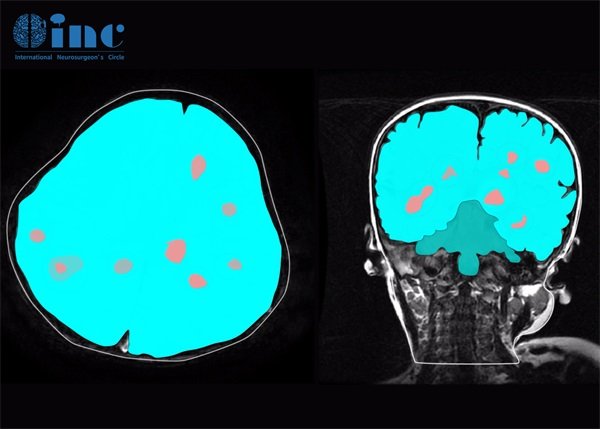

脑出血与海绵状血管瘤mri鉴别?脑出血与海绵状血管瘤在影像学上表现出不同的特征,尤其在MRI检查中。这两者的鉴别对于临床的诊断与治疗至关重要。脑出血通常表现在影像上为高信号区,尤其是在急性期,而海绵状血管瘤则通常为典型的“蜂窝状”结构。

海绵状血管瘤在MRI上呈现出典型的蜂窝状结构,通常较为清晰。在T1加权成像中,其信号呈现为等信号或稍高信号,而在T2加权成像中则往往表现为高信号。

海绵状血管瘤与脑出血的最大不同在于信号的稳定性和血肿的边界。海绵状血管瘤本身为良性血管性肿瘤,通常边界清晰,而脑出血往往显示边界模糊。

通过MRI对比分析,识别海绵状血管瘤奥妙在于其具有脱水成分和明确的血管间质,而这些特征在脑出血中并不显著。